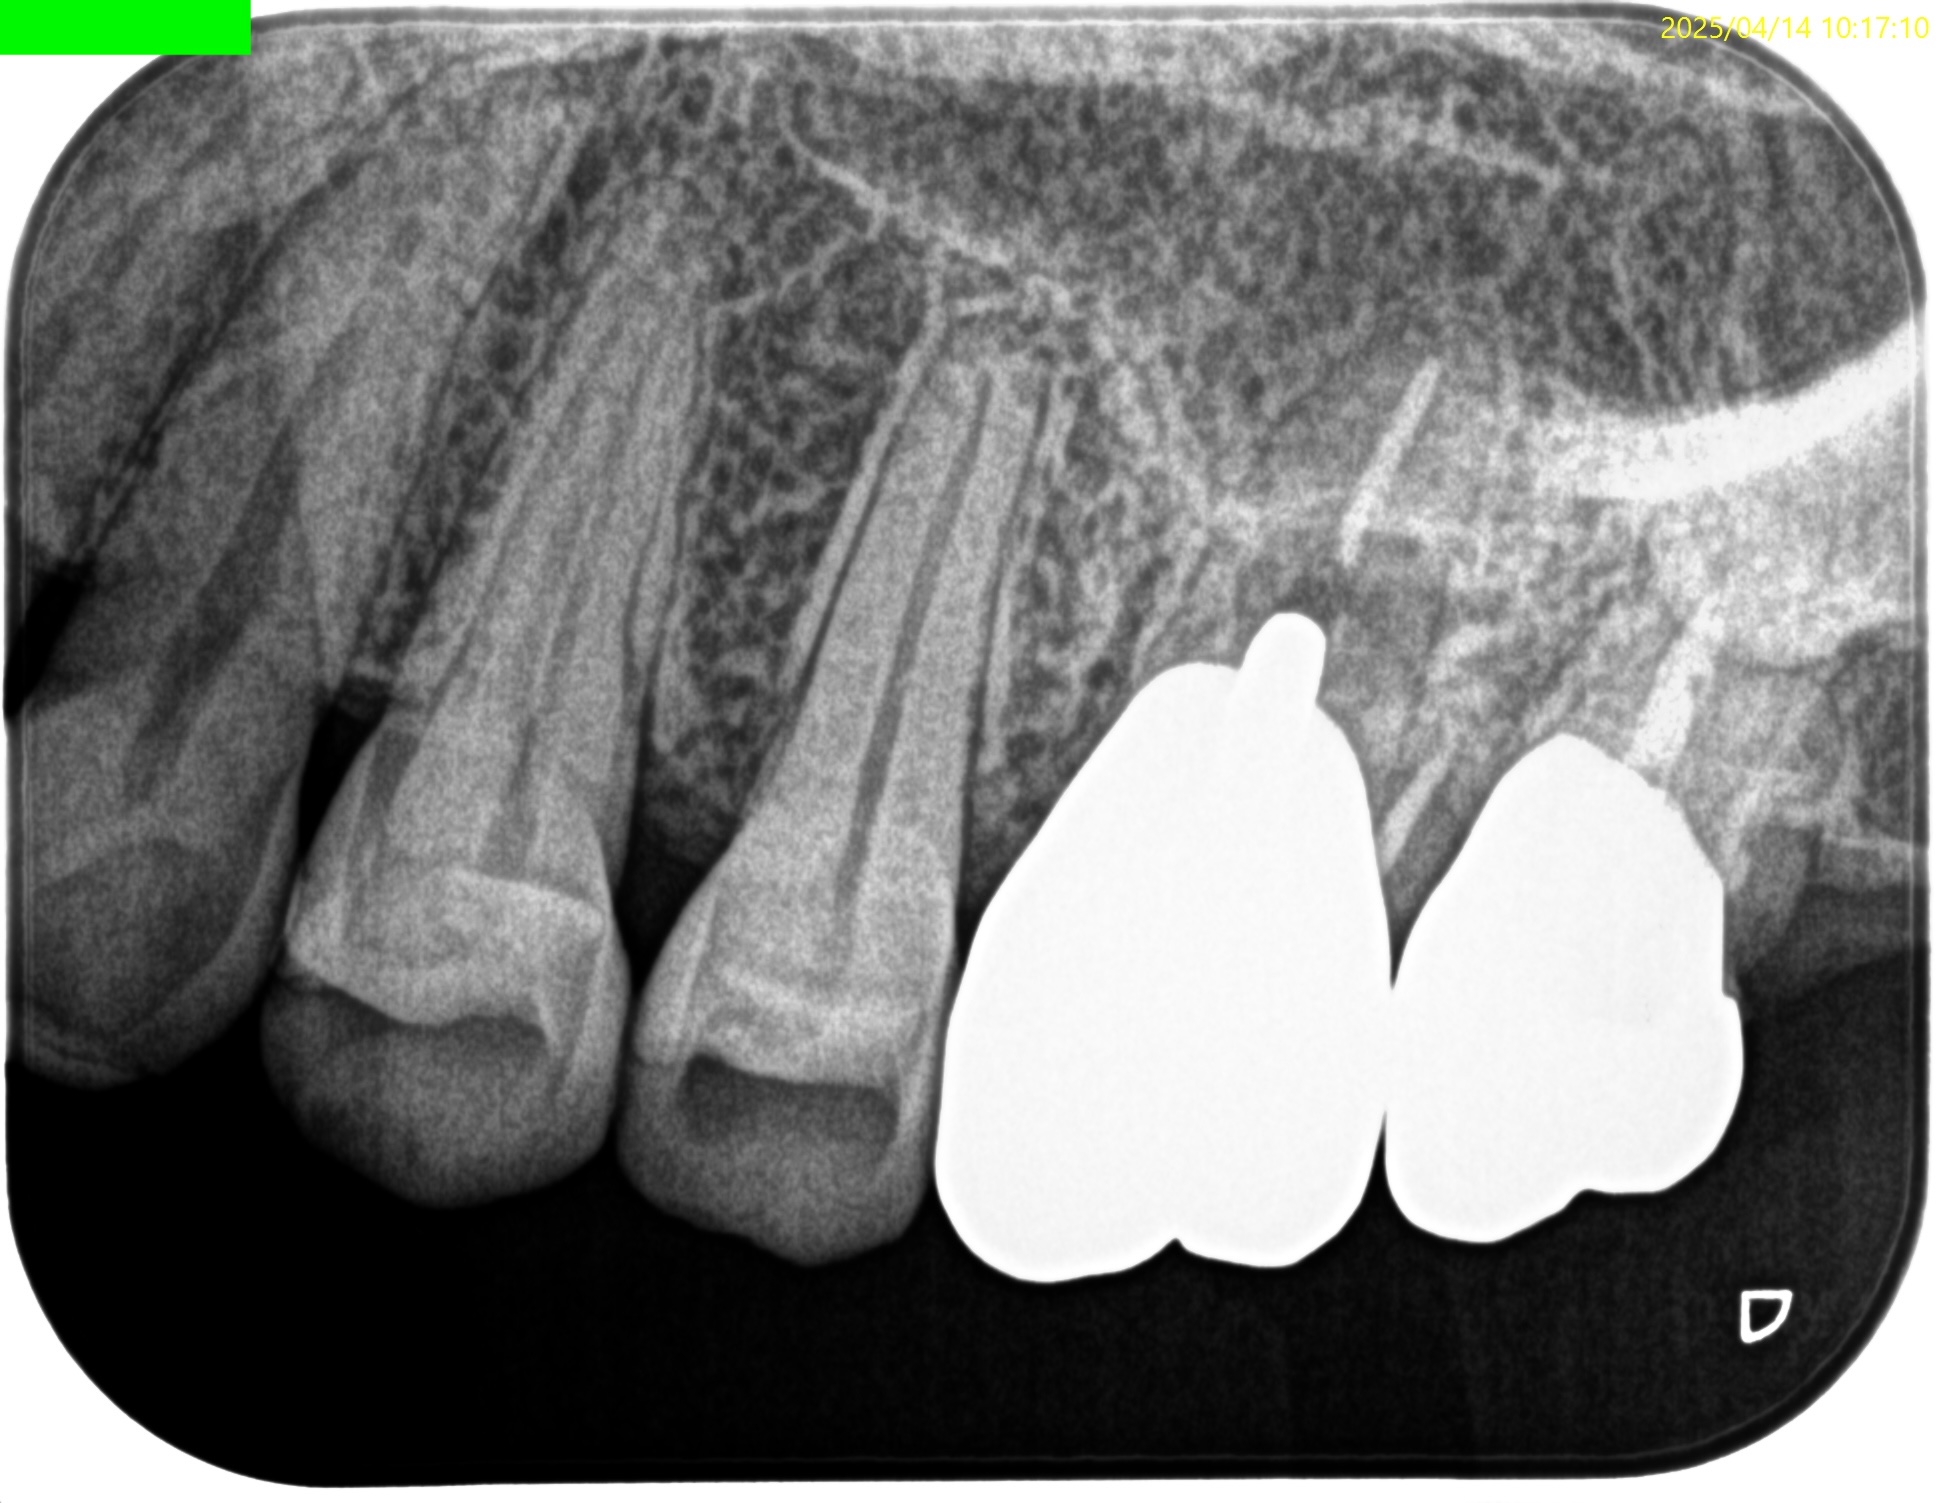

MB

MB2は確実に存在するが石灰化が進み穿通できるか?わからない。

また、Sinus tractが根尖孔外細菌感染の可能性もある。

このことから再根管治療よりも外科治療の方に軍配が上がるだろう。

Pulp Dx: Previously treated

Periapical Dx: Chronic apical abscess

Recommended Tx: Apicoectomy